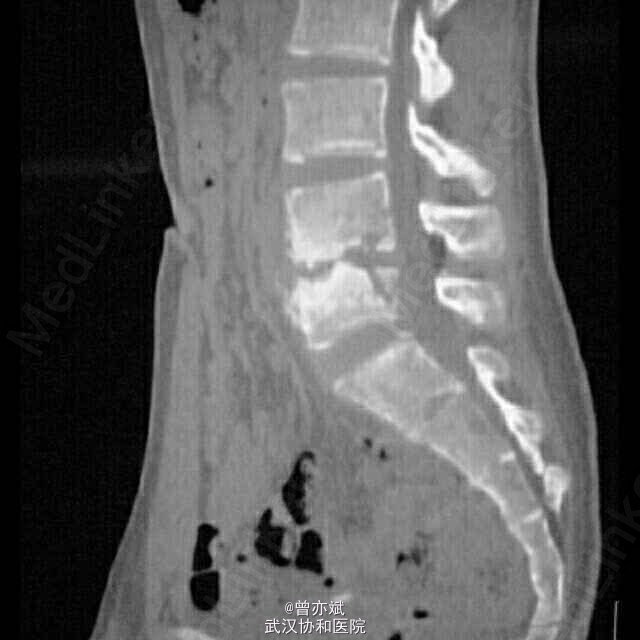

近期,Chi教授等在J Pediatr杂志上发表了一篇儿童脊柱结核的病例报道。病史如下: 患儿为13岁男孩,3个月来体重明显减轻且伴有身体不适,1月前出现左臀部疼痛。体格检查:体温37.8℃,体重减轻6kg,左臀部压痛。脊柱X射线照片示:腰椎椎间盘变窄(图1)。 图1. 脊柱X线片示L4 -L5椎间盘间隙变窄(箭头处) 完善CT检查示:大量脓肿累及胸椎旁区域、左侧腰大肌、髂腰肌、臀中肌和大收肌肌肉,且破坏相邻椎体(图2、3)。 图2. 脊柱CT示:广泛脓肿形成,累及胸椎旁区、左腰肌、髂腰肌、臀中肌和大收肌肌肉(小箭头)。相邻椎体骨破坏(大箭头)。 图3. CT的矢状面示:L4 -L5椎间隙减少,L4和L5椎体破坏 随后给予CT引导下椎旁脓肿穿刺,引流出奶油色的脓液(如图4)。 图4. 椎旁脓肿CT引导下引流出典型的奶油色脓液。 脓液培养结果示:结核杆菌阳性。于是给予患儿抗结核治疗,且达到完全缓解。 结核病仍然威胁着全球人类的健康,其发病率在不同地域有些许差异。脊柱结核,也被称为波特病,可能会造成永久性畸形和神经损害。早期诊断和及时治疗非常重要,但延误诊断的情况并不少见。 结核性脓肿是“冷”脓肿且伴有小范围的炎症浸润,因此,在疾病早期疼痛较为模糊,诊断仍具较大挑战。 (来源:丁香园)